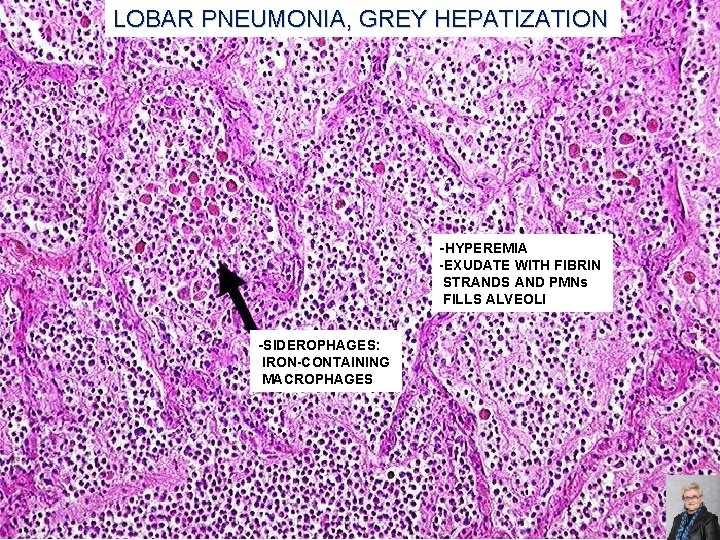

LOBAR PNEUMONIA; CLASSIC STAGES (AS SEEN IN PNEUMOCOCCAL PNEUMONIA) Congestion: �Heavy, boggy, red, hyperemic lungs with many bacteria but few neutrophils Red hepatization: �Massive confluent alveolar filling with RBCs, neutrophils, and fibrin Gray hepatization: �Disintegrating RBCs and fibrinopurulent exudate fill alveoli Resolution: �Macrophages mop up debris and normal function returns 59

LOBAR PNEUMONIA, GREY HEPATIZATION -HYPEREMIA -EXUDATE WITH FIBRIN STRANDS AND PMNs FILLS ALVEOLI -SIDEROPHAGES: IRON-CONTAINING MACROPHAGES 65